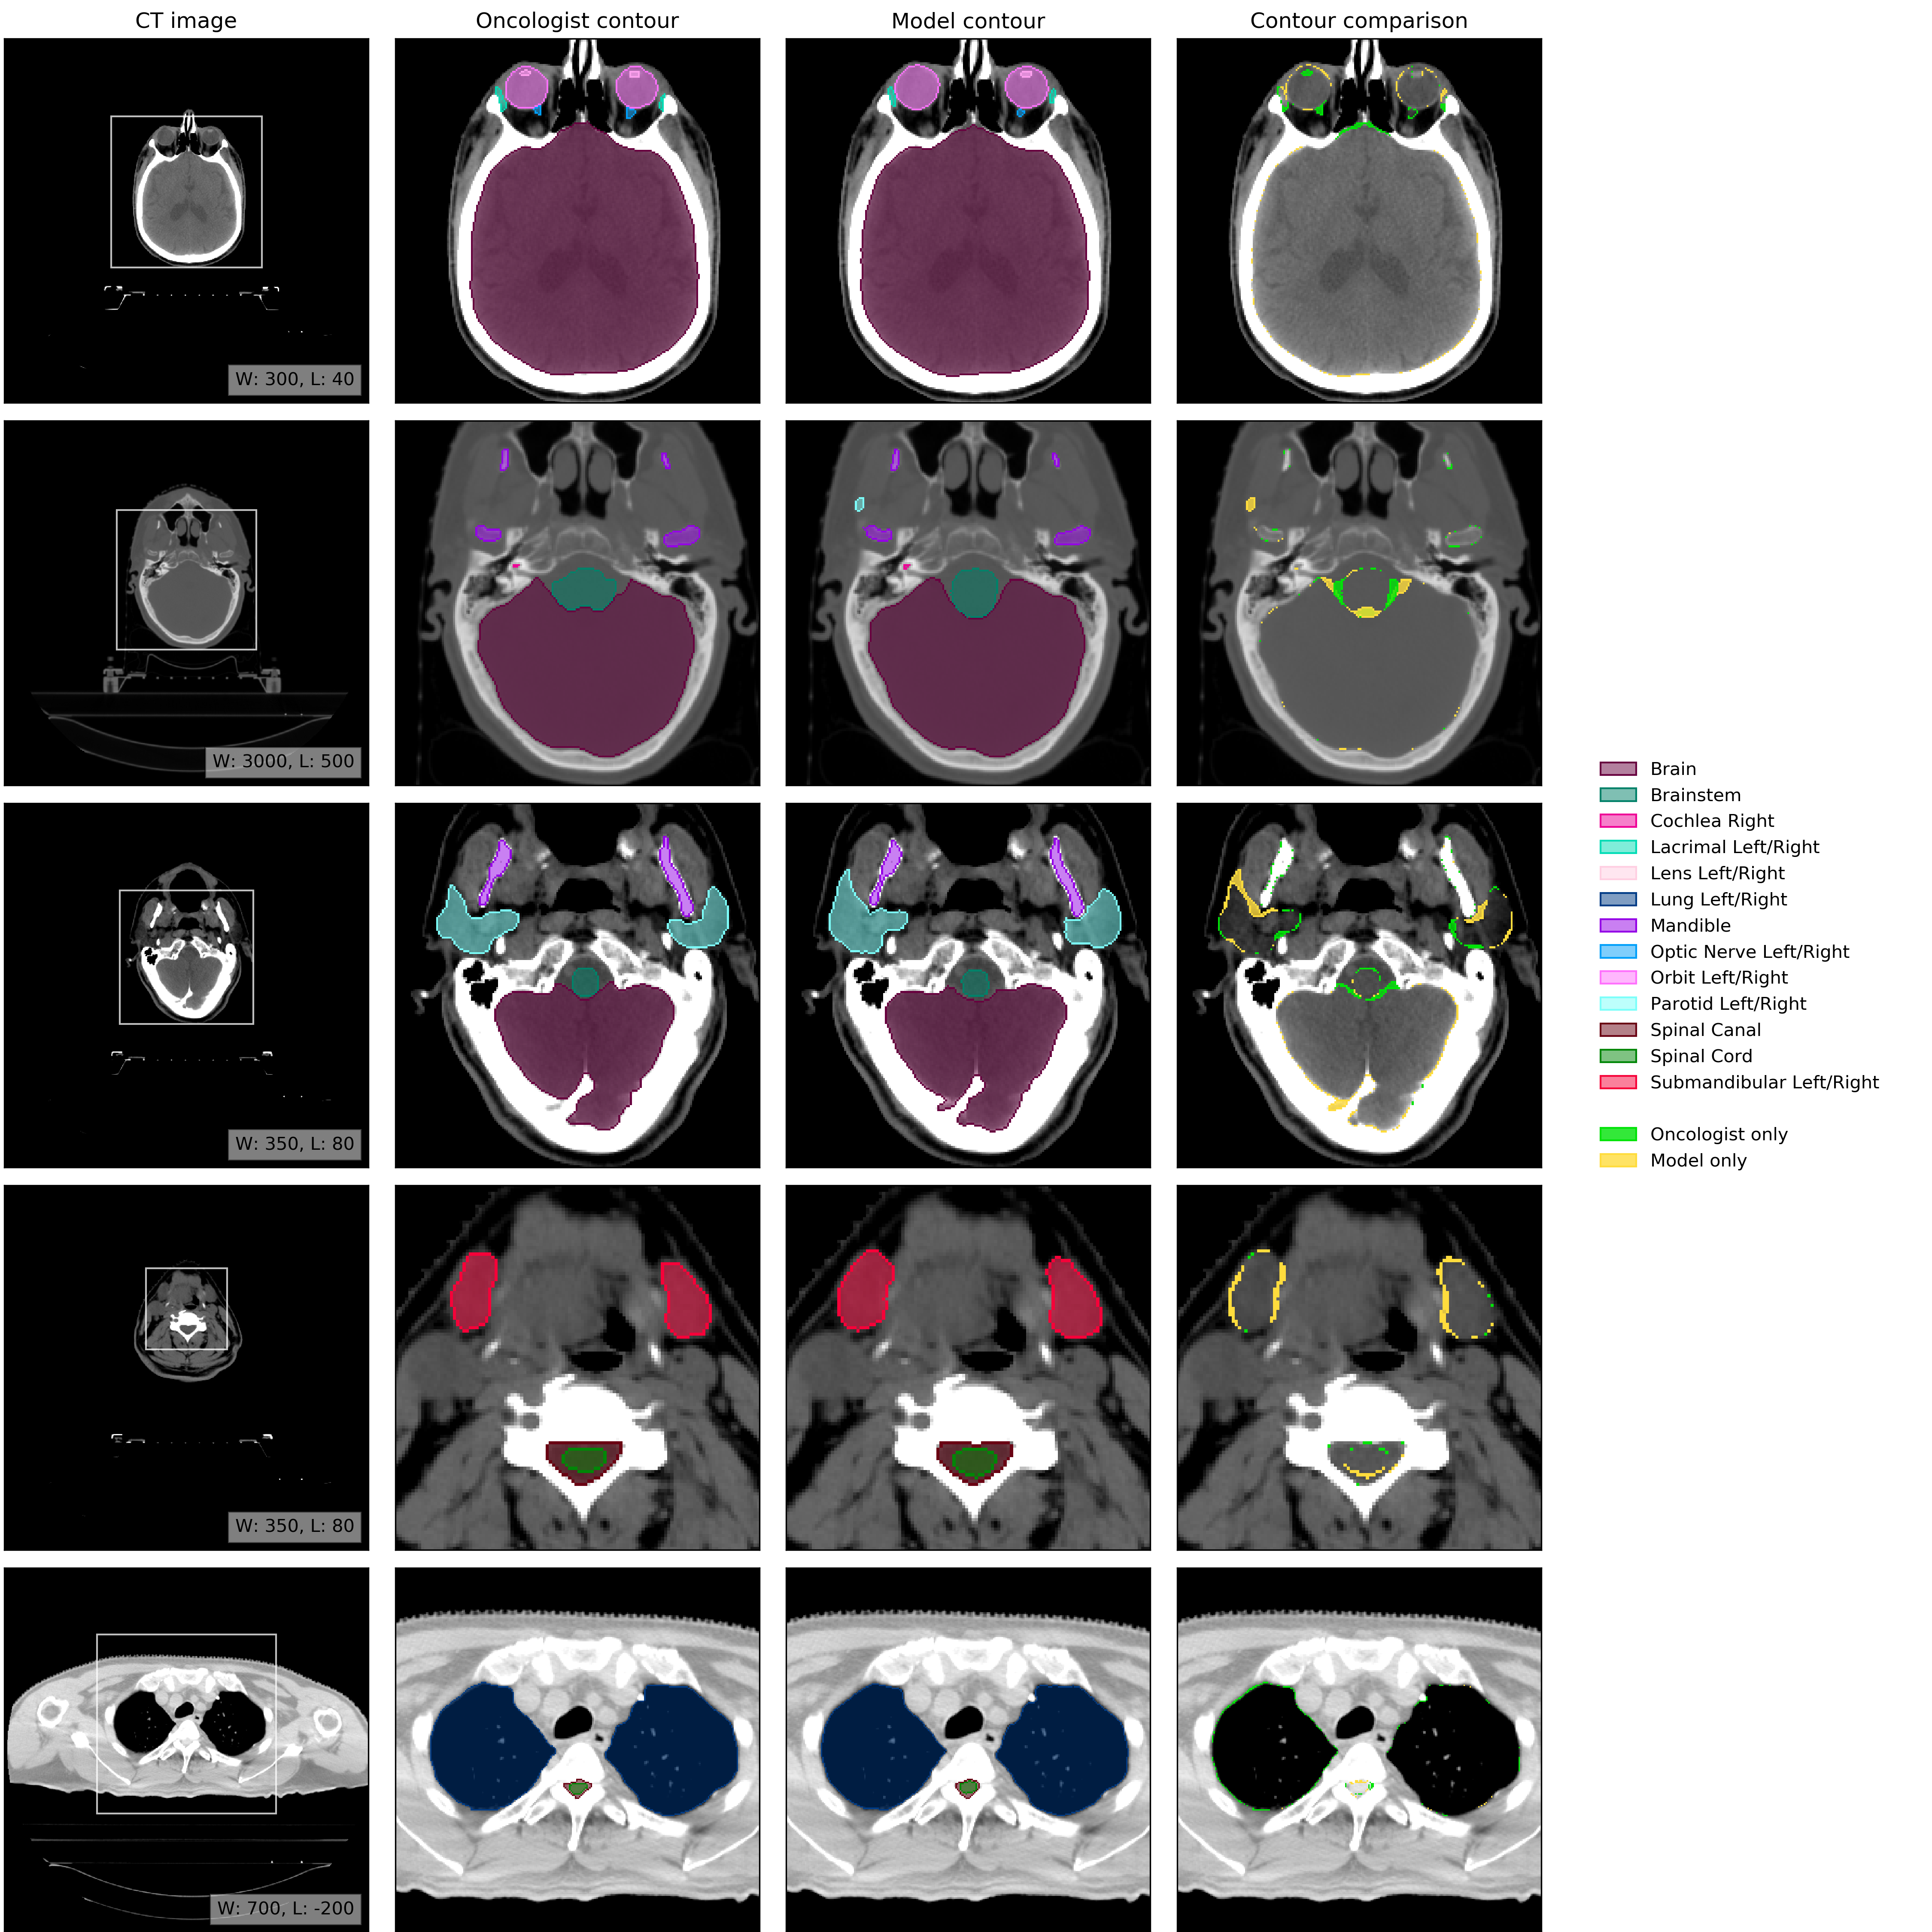

An example of model performance is shown in Fig. 2. We compare our performance (model vs oncologist) to radiographer performance (radiographer vs oncologist). For more information on dataset selection, inclusion and exclusion criteria for patients and OARs please refer to the Methods section.

Refer to caption

Figure 2: Example results. (CT image) Axial slices at five representative levels from the raw CT scan of a 55-59 year old male patient was selected from the UCLH dataset (patient UCLH-20) were selected to best demonstrate the OARs included in the work. The levels shown as 2D slices have been selected to demonstrate all 21 OARs included in this study. The window levelling has been adjusted for each to best display the anatomy present. (Oncologist contour) The ground truth segmentation, as defined by experienced radiographers and arbitrated by a head and neck specialist oncologist. (Model contour) Segmentations produced by our model. (Contour comparison) Contoured by Oncologist only (green region) or Model only (yellow region). Two further randomly selected UCLH set scans are shown in Fig. 12 and Fig. 13. Best viewed on a display.